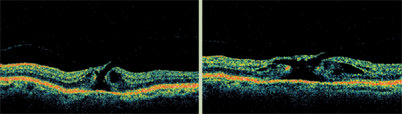

These scans show Stratus OCT images before and after laser treatment for diabetic macular edema. After treatment, the foveal depression returns and the outer retinal layers return to a more normal linear appearance. The outer layers are also less dark, indicating improvement in the sponge-like swelling.

The most common characteristic associated with DME on OCT is sponge-like swelling. In its presence, OCT shows a blunted foveal depression and darker outer retinal layers.

The Cross Hair scan reveals several important characteristics relevant to diabetic macular edema (DME), which is the condition we explore first here.